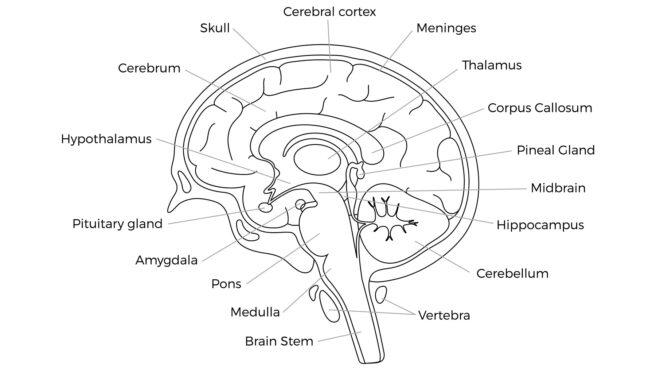

脳科学の進歩はまだまだ進行中のようです。少し前まで「常識」とされていた「学説」が新しい実験により覆されているそうです。少し前に流行った「右脳」と「左脳」の話なども最新の知見では違ってきているようです。そうして世界の人々の脳の違いや傾向が、部分的にですが徐々に分かってきているようです。